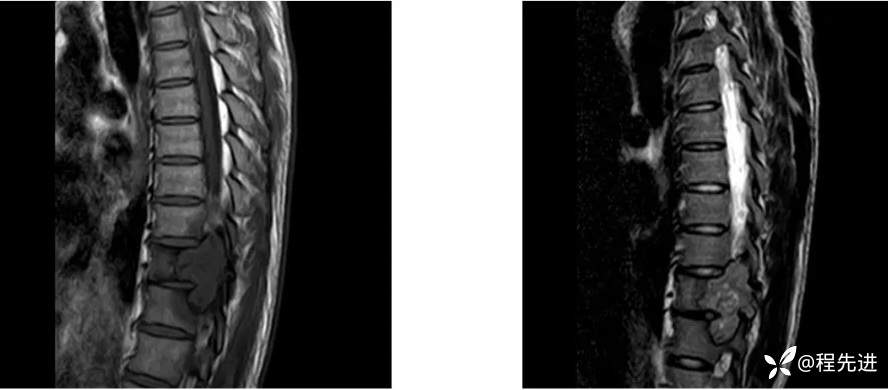

【患者信息】:男,29岁

【现病史及既往史】:双下肢麻木无力5月余,有踩棉感

【检查】